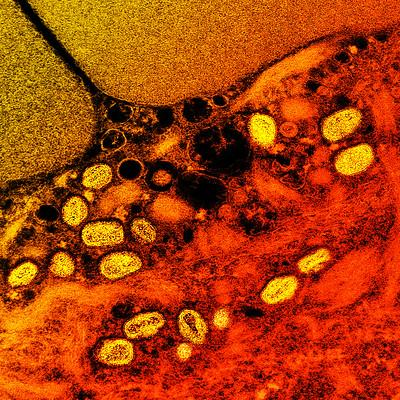

mpox virus

NIAID / Flickr cc